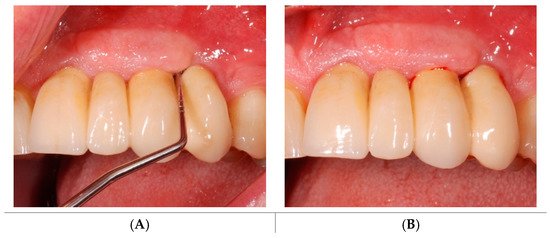

4.4. Study Protocol and Treatment

4.5. Test Substances and Administration